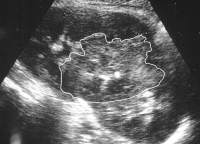

Von Wichtigkeit sind die bildgebenden Verfahren: Sonographie, CT bzw. AUR.

Beispielhaft die Darstellung eines ausgedehnten Nierenabszesses in Sonographie, CT und AUR (Abbildung 6).

Die Abbildung zeigt als weiteres Beispiel die sonographische Darstellung eines ausgedehnten paranephritischen Abszesses (Abbildung 7).